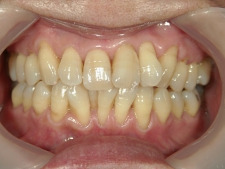

矯正歯科 治療後矯正歯科 プチワイヤー矯正 治療後矯正歯科(プチワイヤー矯正)治療後

矯正歯科 治療後